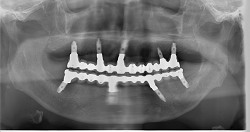

All on 4の症例

レントゲン写真

施術名:上下顎のAll on 4治療

施術の説明:義歯装着患者に対するAll on 4によるインプラント治療

施術の副作用(リスク):オペ後の腫れ、内出血の症状が出る場合がある

施術の価格:4,000,000円